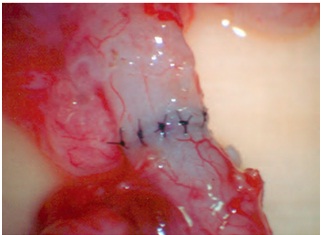

- Nối ống dẫn tinh với mào tinh: Được chỉ định trong trường hợp viêm mào tinh hoàn thường gặp sau nhiễm trùng, về kỹ thuật thường khó khăn hơn (0-30%).

- Cắt ụ núi nội soi: Được chỉ định trong trường hợp nghi ngờ tắc ống phóng tinh.